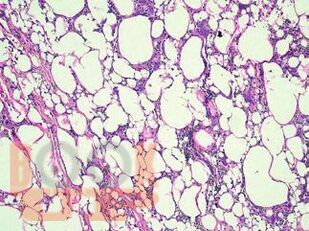

В атласе подробно изложено цитологическое и гистологическое описание всего спектра патологических изменений ткани молочной железы: неопухолевые, пролиферативные процессы, предраковые поражения, доброкачественные и злокачественные опухоли. Кратко представлены данные об этиологии, о патогенезе, молекулярной генетике, клинической картине и лучевых методах исследования различных поражений молочной железы. Подробно описаны дифференциальная диагностика и возможные ошибки морфологической диагностики. Атлас иллюстрирован большим количеством микрофотографий.

Традиционная морфология имеет фундаментальное значение в диагностической патологии. Атлас представляет собой реферативный текст, в котором обобщены имеющиеся на данный момент основные знания о патологии молочной железы, собранные из различных источников, и собственный опыт авторов. Текст построен в виде коротких фраз, постулирующих ключевые моменты различных поражений молочной железы.